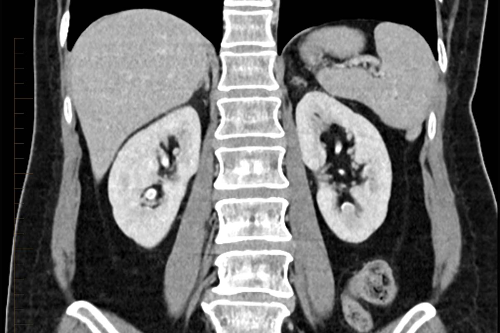

3.CT(전산화 단층촬영)

흉부 CT 촬영은 흉부 엑스레이보다 폐암을 발견할 수 있는 확률이 높고 이로 인해 폐암을 조기 발견하여 사망률은 낮출 수 있습니다. 저선량 CT는 방사선 조사량을 기존 CT에 비해 현저하게 줄이는 검사 방법으로 방사선에 노출되는 위험을 줄일 수 있습니다. 이 검사 방법은 해상도는 저선량이라서 기존 CT에 비하여 감소하지만 병변 유무를 관찰하는 데는 충분하며 간편한 검사입니다. X-ray에서 발견이 어려운 초기 폐암의 경우 흉부 CT 촬영을 통해 조기에 발견할 수 있습니다.